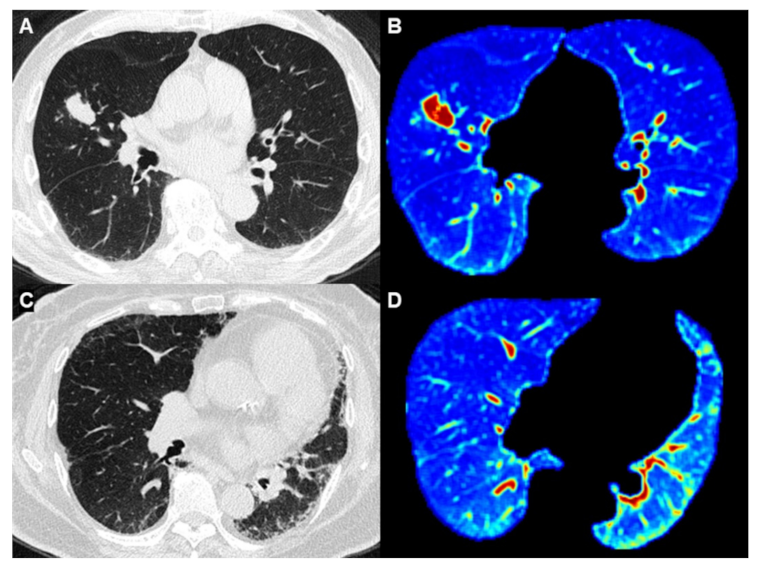

Figure 4.

Comparison between IPF patients with and without lung cancer. (A,B) Images from an 87-year-old man who was a heavy smoker with IPF. (4A) HRCT showed an adenocarcinoma in the middle lobe of the right lung. (B) Whole-lung texture analysis revealed energy: 2.56 × 1012 and Kurtosis: 29.13 (C,D) Image from a 74-year-old woman who was a nonsmoker and was diagnosed with IPF. (C) HRCT showed pulmonary fibrosis without lung cancer (D) Whole-lung texture analysis revealed energy: 1.21 × 1012 and Kurtosis: 17.62.